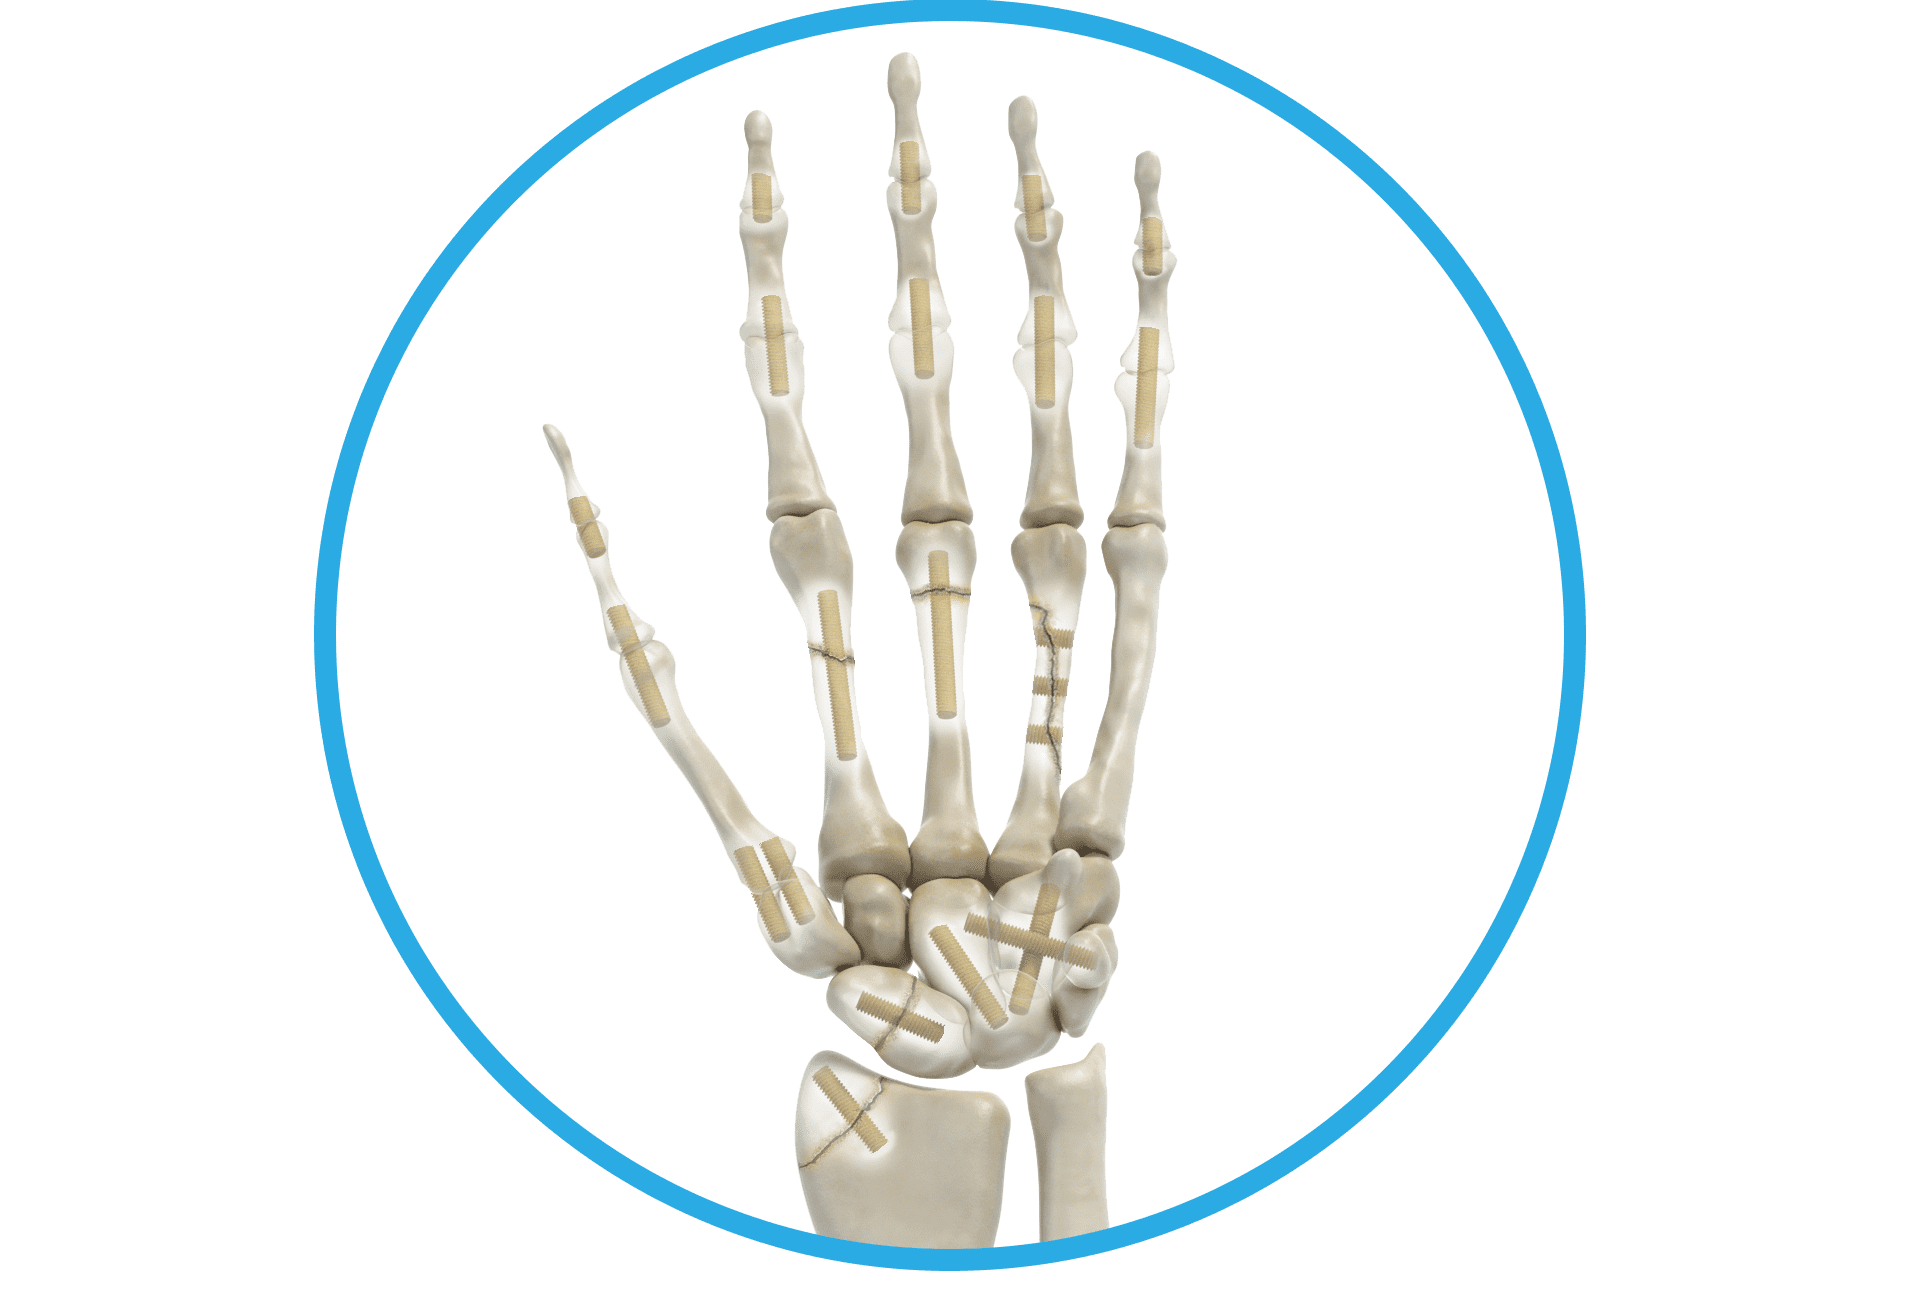

Als Shark Screw® Hero nützen Sie die natürlichen Vorteile intakter Havers-Kanäle und Co-Spaces in der Shark Screw®. Damit setzen Sie eine solide Knochenbrücke mit feinsten Kanälen und Co-Spaces über die und in welche Zellen wandern können. Dadurch wird primäre Knochenheilung zwischen Shark Screw® und Empfängerknochen sowie ein Remodeling der allogenen Knochenschraube möglich.1 Von diesen Eigenschaften profitieren Sie und Ihre Patienten vorzugsweise bei Arthrodesen, Frakturen, Pseudarthrosen und Umstellungen. Einen Auszug aus relevanten Studien zur Shark Screw® finden Sie hier.